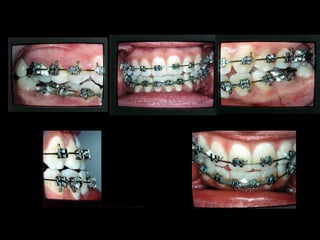

Arcada Superior: Forma oval Paladarprofundo Totalidad de órganos dentarios a excepción de tercer molar izq. Restauraciones deficientes Arcada Superior: Forma oval Paladar profundo Totalidad de órganos dentarios a excepción de tercer molar izq. Restauraciones deficientes Frente: Línea media desviada Mordida cruzada anterior Frente: Línea media desviada Mordida cruzada anterior Arcada Inferior: Forma ovalada Colapso posterior Ligero apiñamiento de anteriores Rotación de premolares Arcada Inferior: Forma ovalada Colapso posterior Ligero apiñamiento de anteriores Rotación de premolares

Modelos vista lateral prequirúrgica Modelosvista lateral prequirúrgica 6 6 3 3 Clase III molar y caninaClase III molar y canina